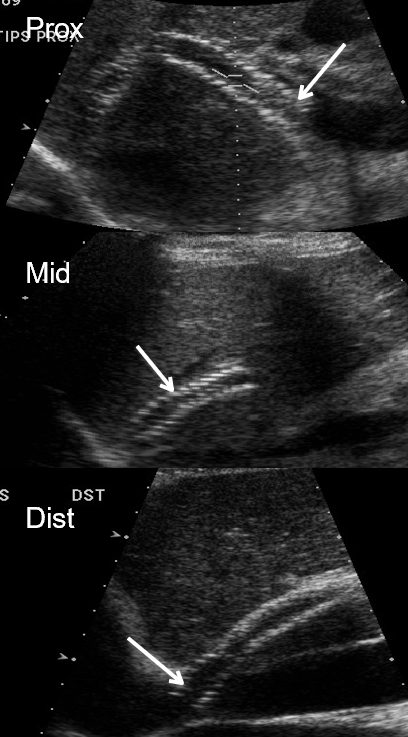

what are the required sampling sites for TIPS?

MPV (direction & wavefom)

PROX : portal end of TIPS (insertion of MPV)

MID stent

DISTAL : hepatic venous end, outflow (inserts into IVC)

portal branches if visualized

what does this show?

prox TIPS velocity → HIGH

mid TIPS velocity → low

MPV velocity → low

Conclusion : PT required a TIPS revision

downstream stenosis reduces forward flow → velocity drops upstream

low velocities

direction

upper right image of MPV → hepatofugal flow when MPV should be hepatopetal